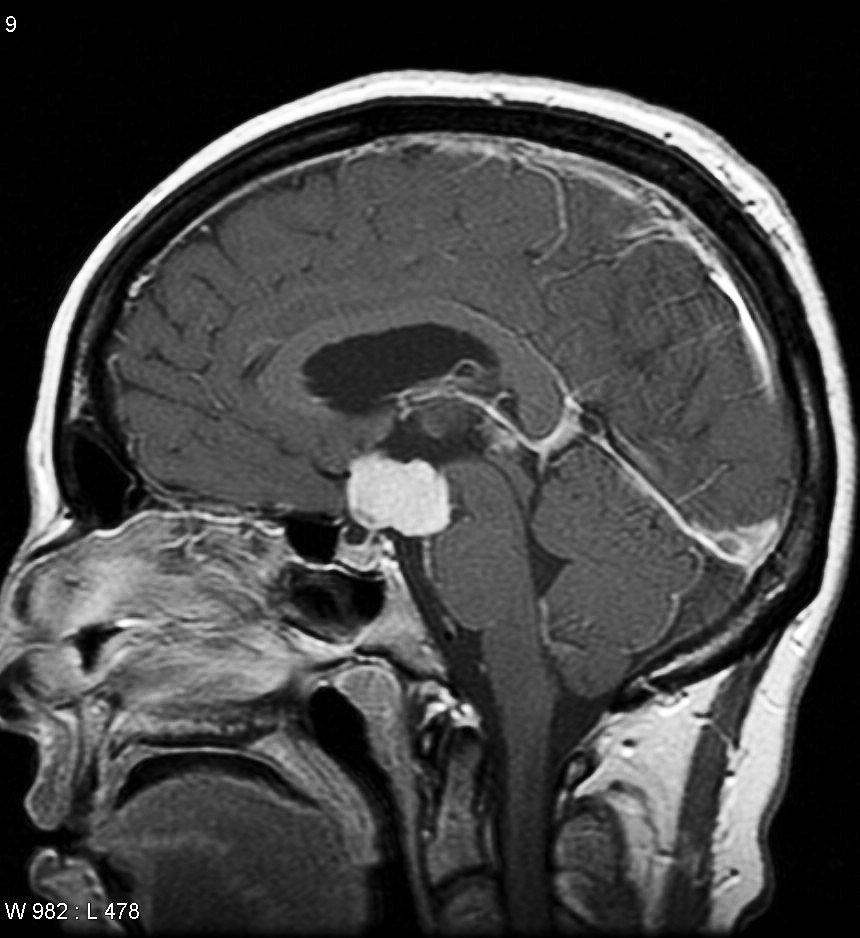

Craniopharyngioma example.

And I was elated when Dr. X informed my parents that the second scan revealed a tumor located at the base of my brain. He called it a craniopharyngioma, and said that although it was benign, this type of tumor could cause headaches, hormonal imbalances and vision problems if left untreated.